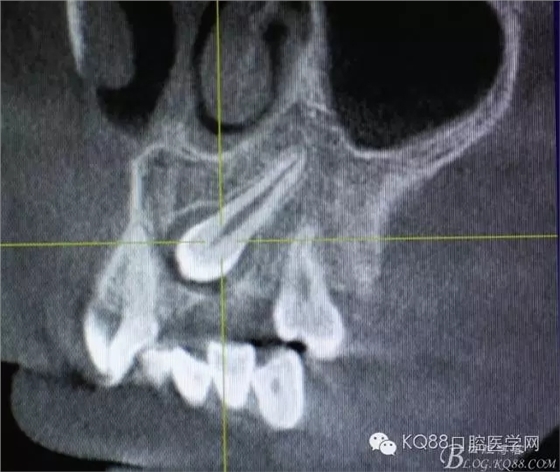

圖1.術(shù)前的cbct影像檢查:23位于腭側(cè)、牙齒位置比較高。